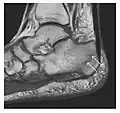

Figure 7: Fatigue fracture of the talus in a 25-year-old male basketball player with right hind foot and ankle pain, without history of trauma, and a normal initial radiograph (not shown). (a) One-month followup lateral radiograph shows normal appearance. (b) Sagittal T1-weighted MRI shows an irregular fracture line (arrow) within an ill-defined area of hypointensity corresponding to bone marrow edema.[1]